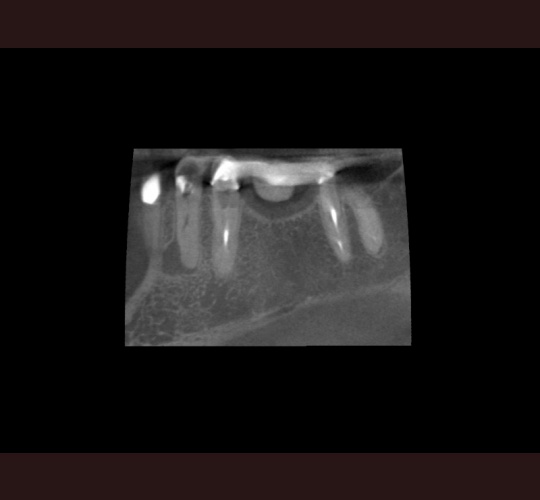

CBCT Diagnosis: Case #9

A CBCT was not necessary to identify multiple roots in this lower 1st bicuspid but was able to help us identify the actual root configuration and to locate all three canals with relative ease and without over enlarging and weakening the per cervical dentin.